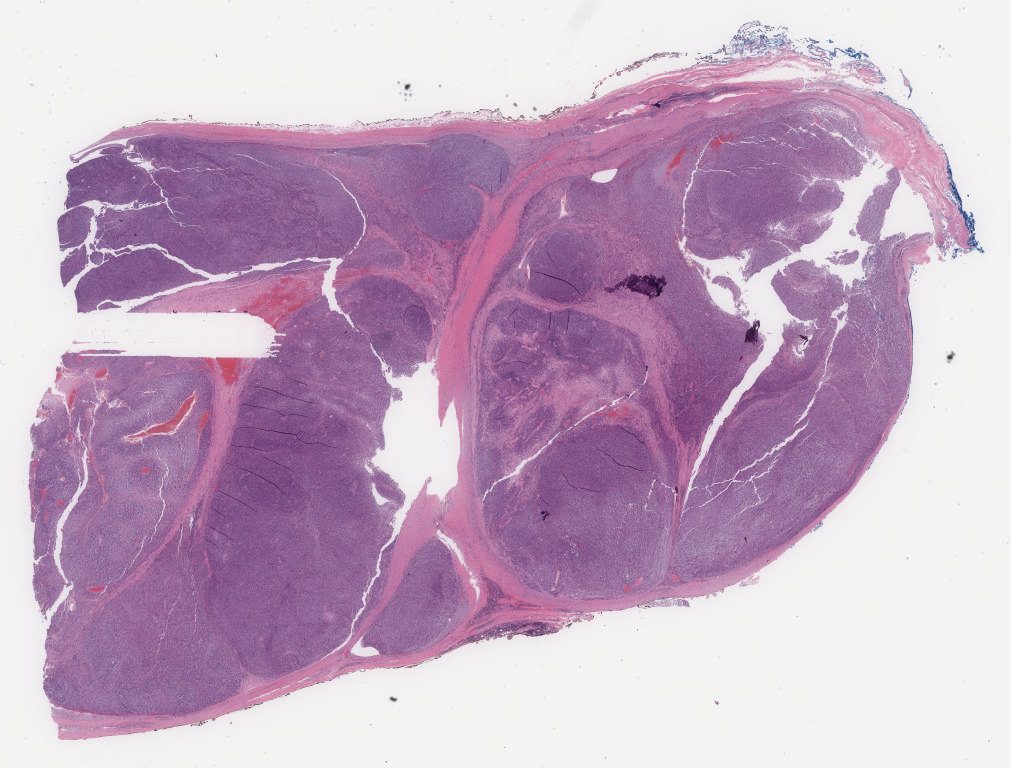

he.svs

85655

x

65015

@

40X